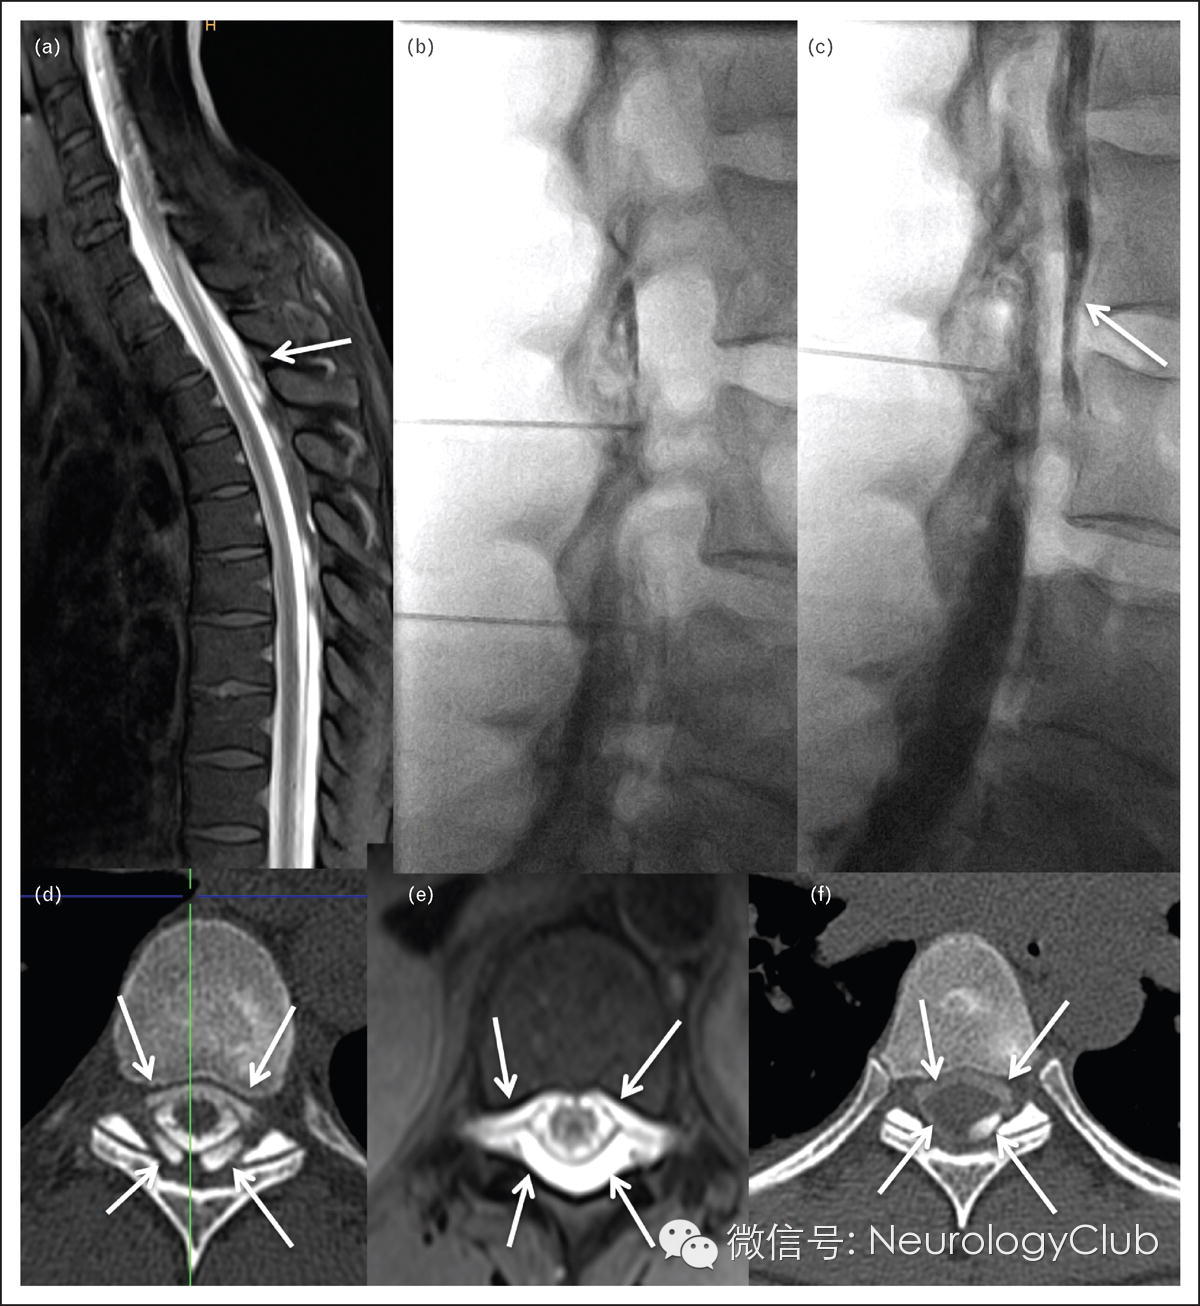

图4 低颅压硬膜外血贴术

42岁女性,分娩时硬膜外麻醉继发低颅压,在X线引导下行硬膜外血贴术。三次盲法硬膜外血贴术后症状无明显好转。腰椎注射0.5ml钆剂和15ml Solutrast(一种水溶性对比剂)后行MR脊髓造影和CT脊髓造影。在胸椎节段(箭头,图a,d,e)可见最明显的硬膜外对比剂积聚。第二天,对比剂都已经集中于硬膜外腔中,但是仍有四个小孔(L4/5,L3/4,L2/3水平)需要确认造影剂是否到达胸段硬膜外腔中(图b,c)。图c中,对比剂充满了腹侧硬膜外腔(箭),在此位置数秒内注入35ml血液。在硬膜外血-对比剂注入后行T6/7水平CT扫描,证实血-造影剂进入到正确位置(箭,图f)